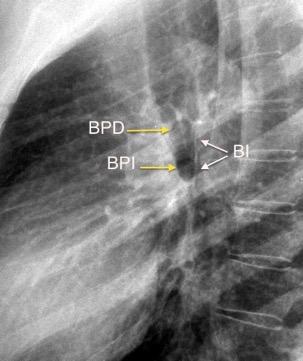

Anatomía

BPI: 75% de normales

La imagen es probable que represente al BPI, a la altura del nacimiento del BLSI.

AV,. The left lateral radiograph of the chest. Part One. Med. Radiogr. Photogr.1979.

La presencia de tumor o ganglios rodeando el BPI hace que este aparezca como mucho más nítido y definido.

Carcinoma microcítico..

Parálisis frénica. Atelectasia parcial de LSI.

Whitten CR. A Diagnostic Approach to Mediastinal Abnormalities. Radiographics 2007 / Marano R et al. Cardiac Silhouette findings And mediastinal lines and stripes. Chest. 2011

En el normal, el bronquio intermediario (BI) aparece en la proyección lateral, como una línea fina vertical que cruza el bronquio del LSI en su unión con el principal. (BPI) Engrosamiento del bronquio intermediario (BI)

97% de normales

Causas

Fallo cardiaco

Ca de pulmón

Metástasis

Linfoma

Sarcoidosis

Castleman

Schnur MJ et al.. Thickening of the Posterior Wall of the Bronchus Intermedius. Radiology. 1981